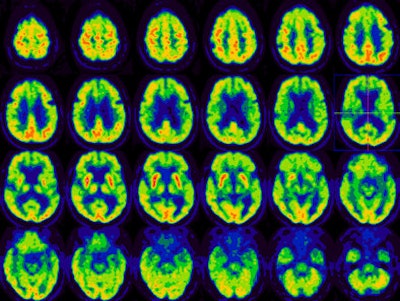

A study from the Cleveland Clinic to investigate brain metabolism of patients with amyotrophic lateral sclerosis (ALS, or Lou Gehrig's disease) has shown that PET imaging may be useful in distinguishing typical dementia syndromes, such as Alzheimer's disease and frontotemporal dementia, from atypical cortical changes.

In addition, PET scans demonstrated that the ALS patients with cognitive impairment represent a heterogeneous group.

Although they may have specific dementia syndrome, such as Alzheimer's disease, frontotemporal dementia, or aphasia syndrome, the majority of patients are either normal or show diffuse cortical hypometabolism.